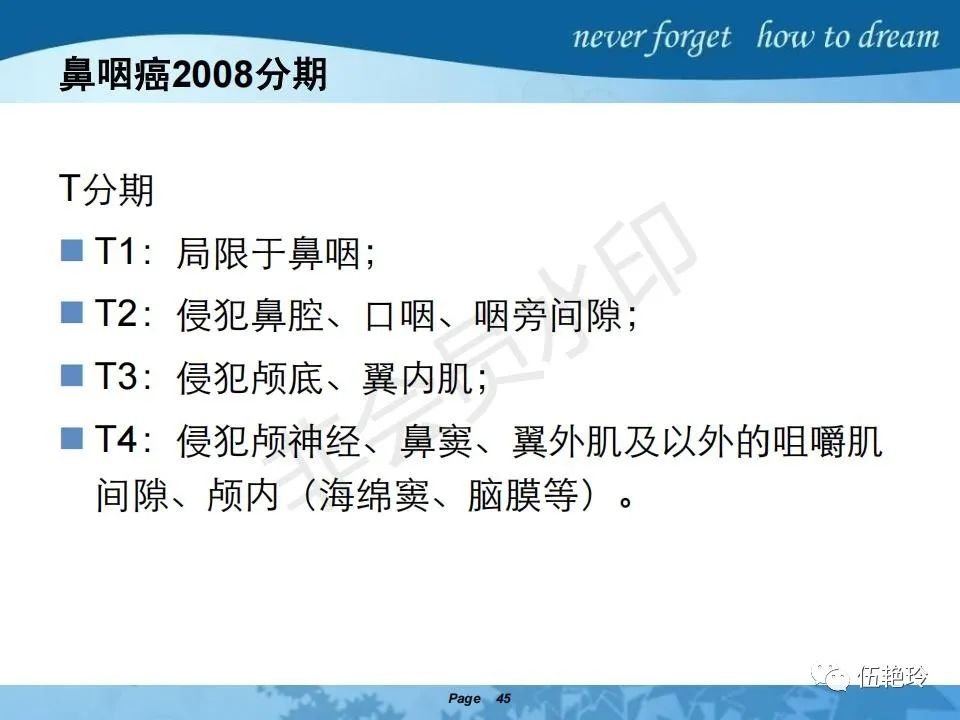

2.31 向上颅内:①鼻咽顶壁→破裂孔(岩尖、斜坡)→蝶窦、海绵窦;②鼻咽顶壁→蝶骨基底部→蝶窦、海绵窦;③鼻咽侧壁→茎突前间隙→蝶骨大翼(卵圆孔)→海绵窦;④鼻咽侧壁→茎突前间隙→翼腭窝→ 颞下窝;⑤鼻咽前壁→鼻腔→翼突、翼腭窝→眶下裂→眶尖→海绵窦;⑥鼻咽前壁→鼻腔→上颌窦、筛窦;

2.32向下颈椎:①鼻咽后壁→斜坡、颈椎→颅内;②鼻咽下壁→口咽(淋巴结多见)→下咽;③鼻咽下壁→口咽(淋巴结多见)→斜坡、颈椎。